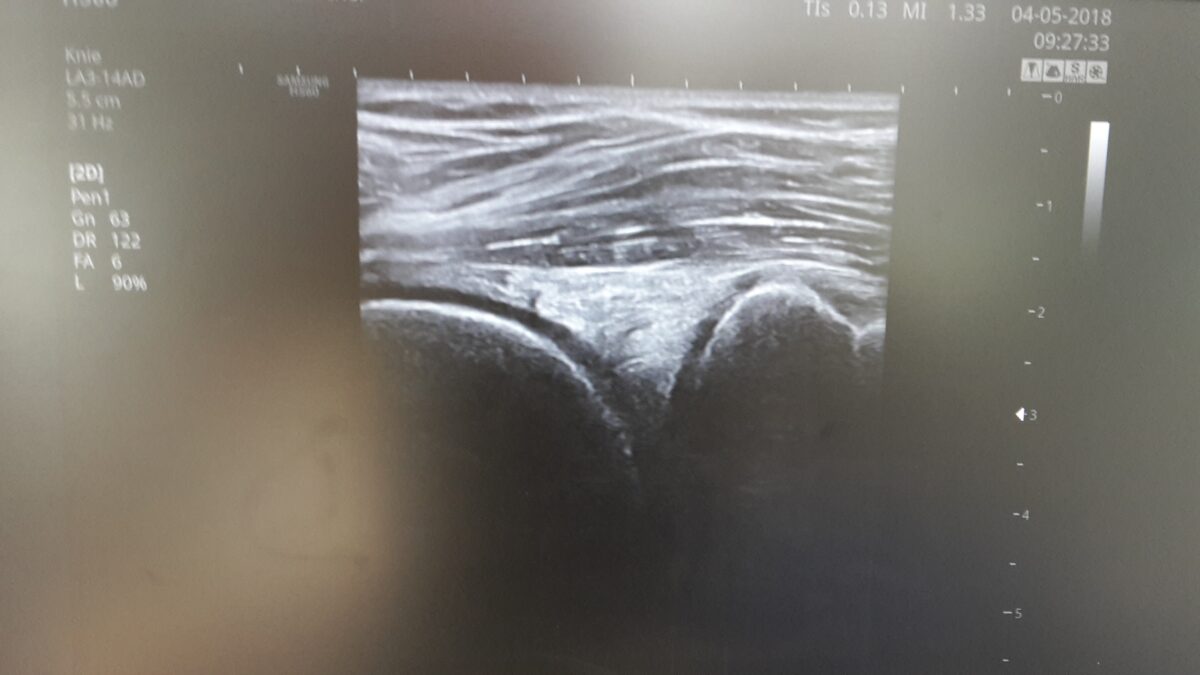

Meniskusdiagnostik